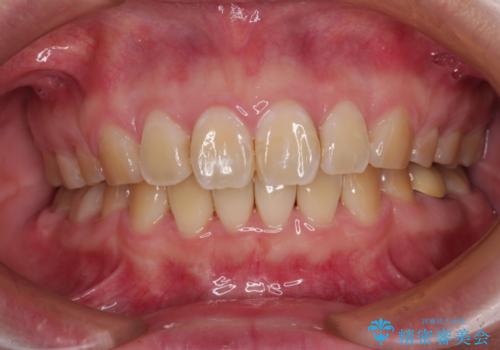

【インビザライン】マウスピース矯正希望。

担当医 河口智英